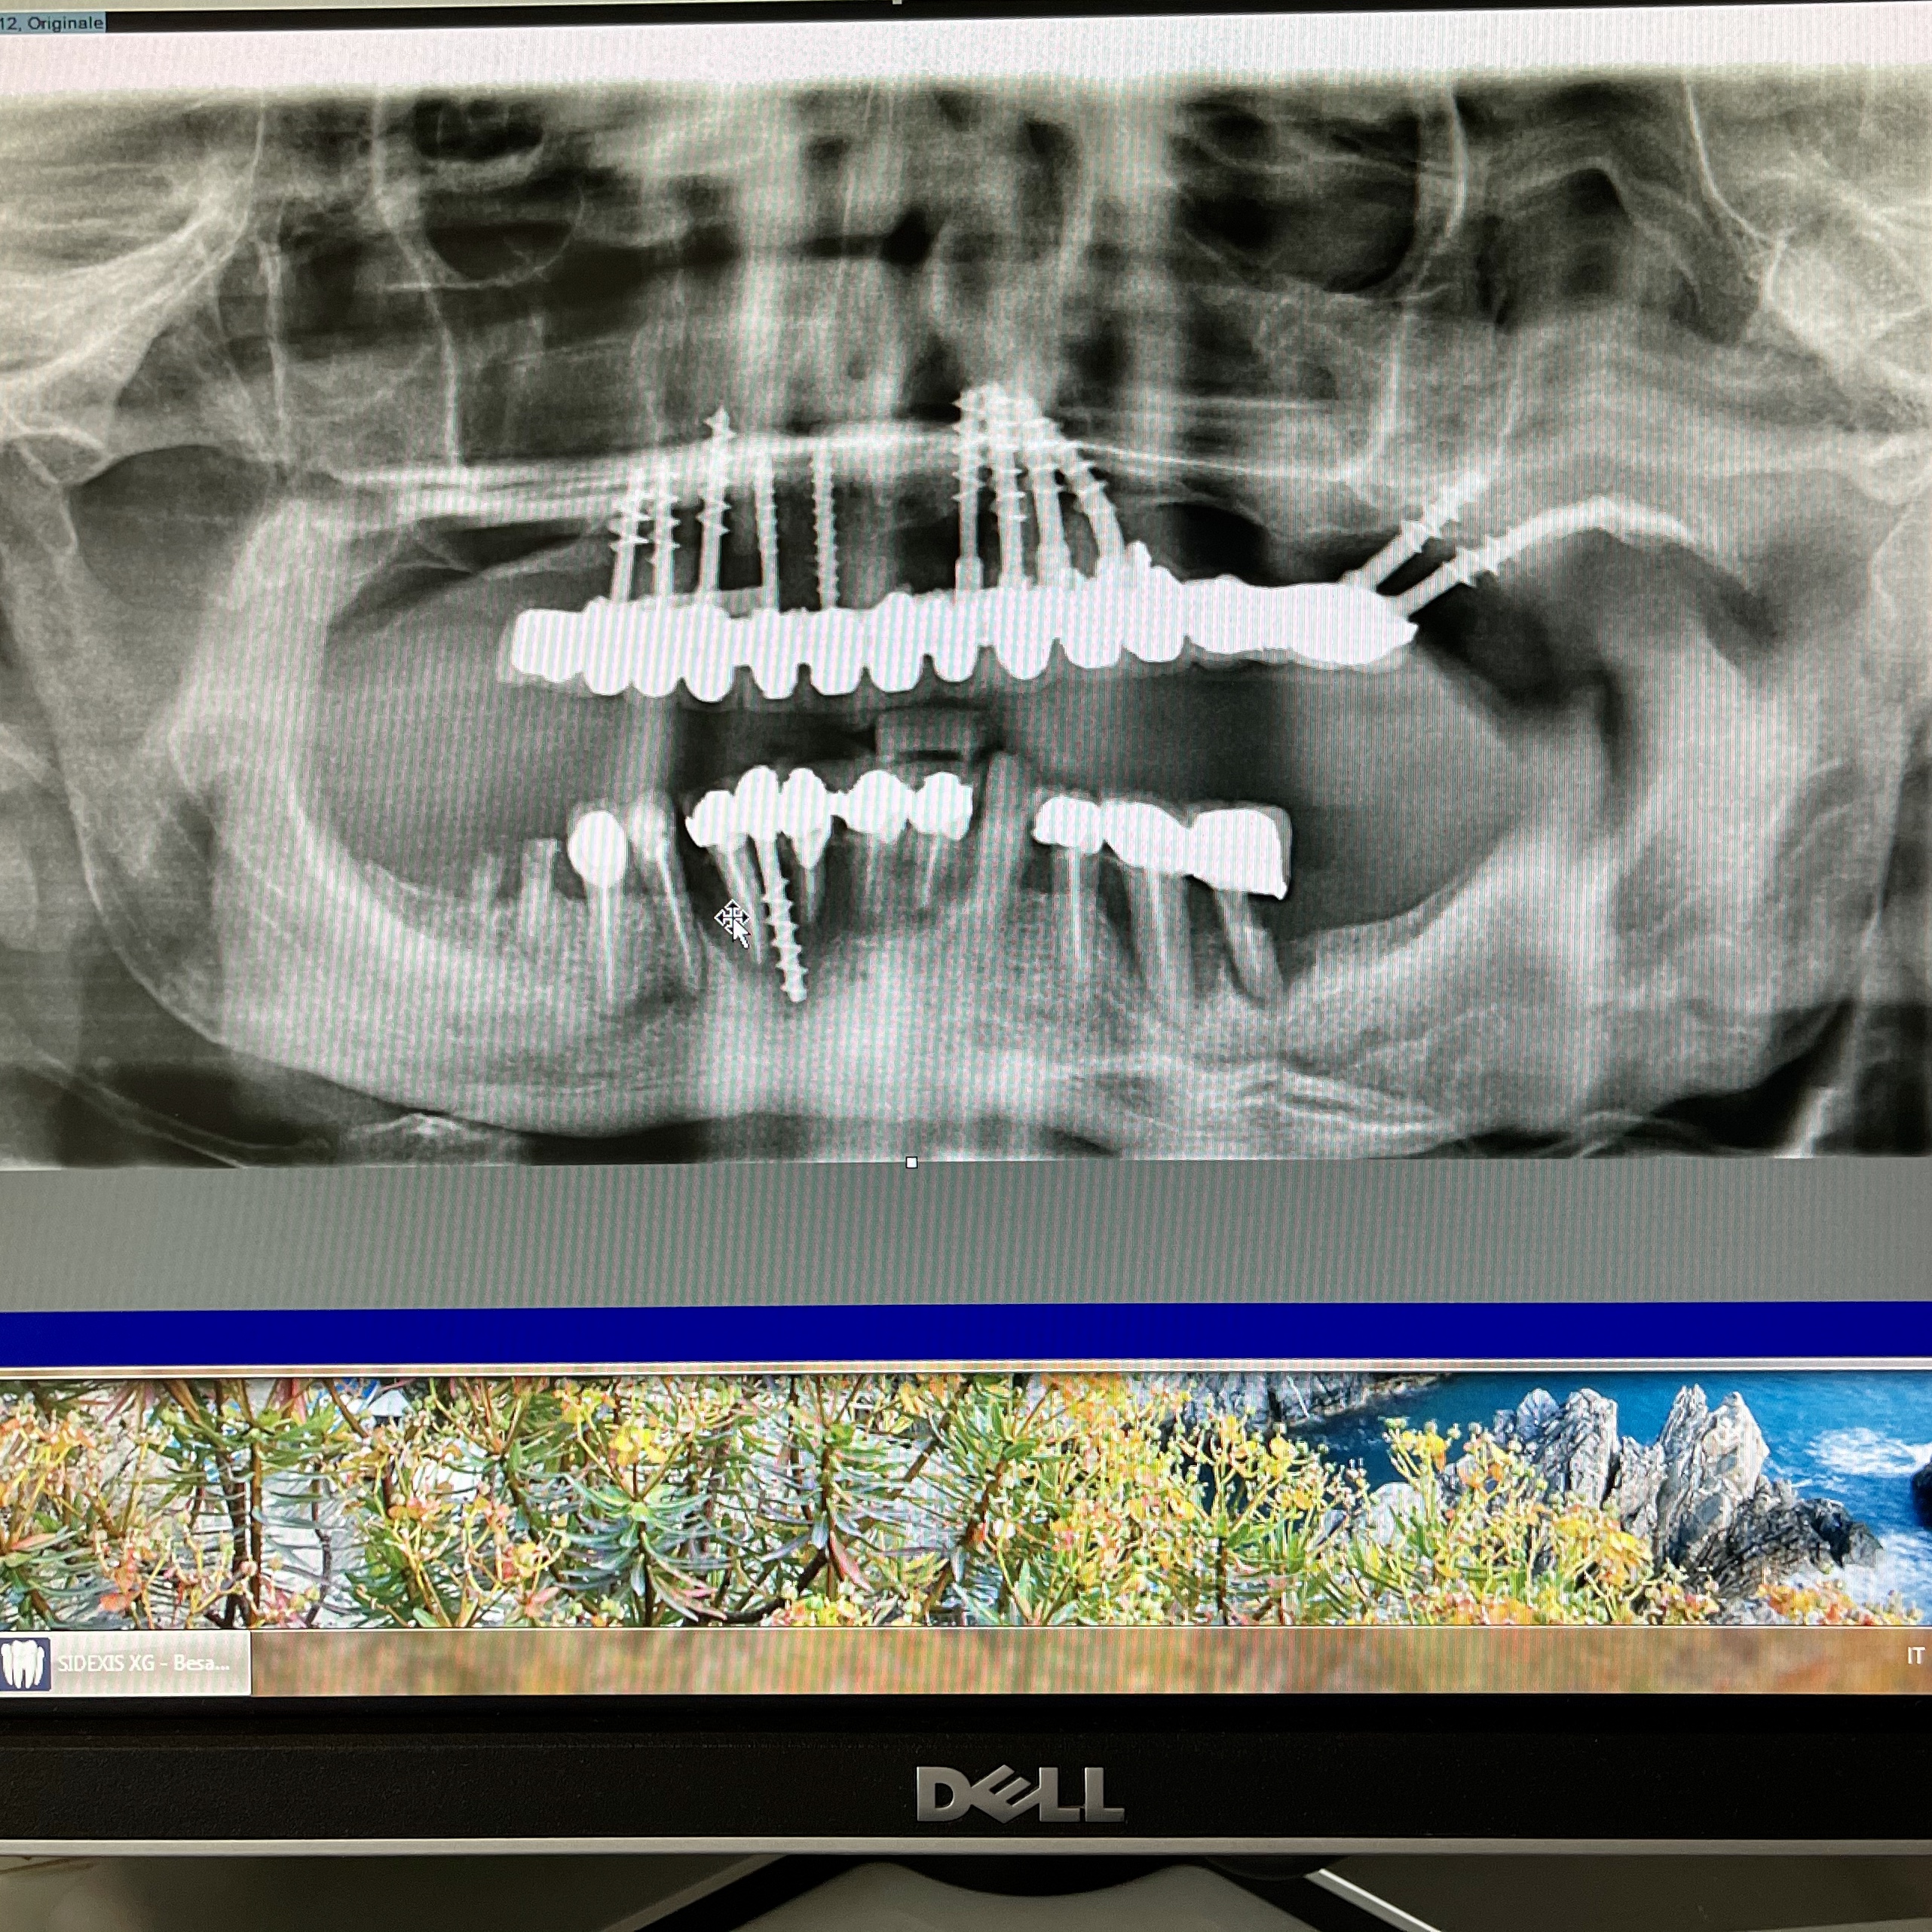

6 - CONFRONTO TRA IMPLANTOLOGIA OSTEOINTEGRATA E IMPLANTOLOGIA DI SCUOLA ITALIANA.

CONSEGUENZE DELLA DIVERSA OPERATIVITA’ TRA LE DUE METODICHE: Durante la progettazione, durante l’inserimento, durante la guarigione e dopo la guarigione.